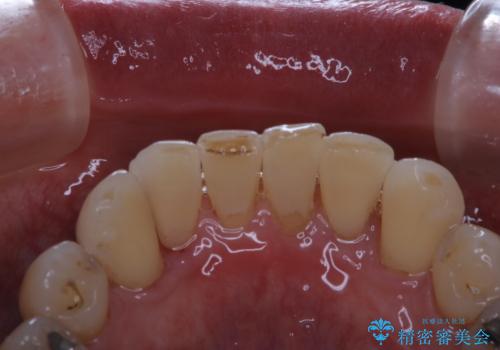

- インビザラインでの矯正中も、コーヒーを頻繁に飲むためステインが気になるとのことでした。PMTC60分コースでなんとかクリーニングを行いました。

矯正治療中も定期的に歯科医院にてPMTCを受けて、お口のケアを行うことをおすすめします。

PMTCは30分コース・60分コースがあります。

30分コースでは主に前歯をメインに行います。

60分コースでは全体的に行います。